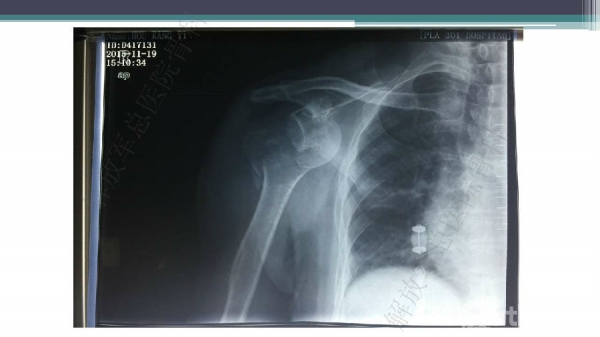

导 语:肱骨近端骨折仍是最常见的骨科损伤之一,尤其好发于老年人群。移位型肱骨近端骨折通常需要手术治疗,但是由于骨折粉碎、骨质较差,手术治疗往往会比较困难。随着锁定钢板的发明,使得并发症显著降低。但仍存在一些问题,对于内侧皮质不连续缺乏内侧可靠支撑,合并老年骨质疏松的病人,锁定钢板吊臂样结构就无法满足力学要求,随着康复锻炼可能出现断板、断钉、螺钉切出肱骨头等并发症。本期解放军总医院骨科专家们对老年肱骨近端骨折的问题与创新手术技术进行了详细讲解。